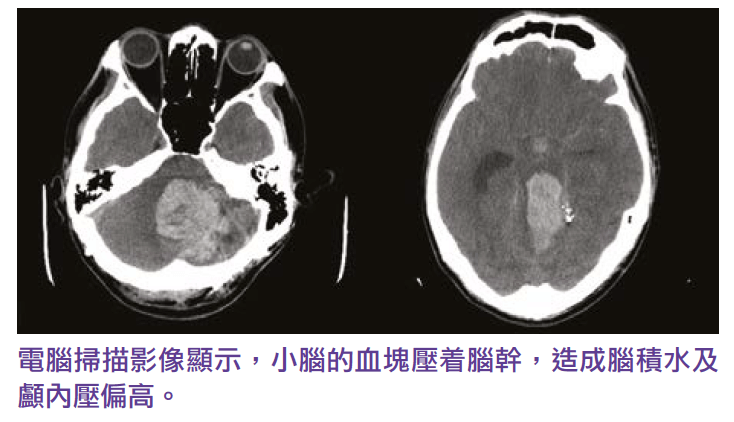

Three years ago, a 46-year-old Ms Leung, has headaches for three or four weeks, consulted his family doctor when arrived at the emergency room, the symptoms disappeared after taking the medication. Later, the brain CT scan report from the public hospital no abnormal finding. so the patient and her family thought that everything was fine. Two weeks later, suddenly felt a severe headache at home and quickly fell unconscious. After emergency treatment in a public hospital, CT scans and cerebral angiography showed that Ms. Leung’s cerebellum had suffered a severe hemorrhagic stroke due to the rupture of a cerebrovascular aneurysm, and that a blood clot in the cerebellum pressed against the brainstem, resulting in hydrocephalus and high intracranial pressure and dilated pupils. A neurosurgeons need to clip the blasted cerebrovascular aneurysm, remove blood clots from the cerebellum, and drain the ventricles through emergency craniotomy to reduce the pressure on the compressed brainstem and intracranial pressure.